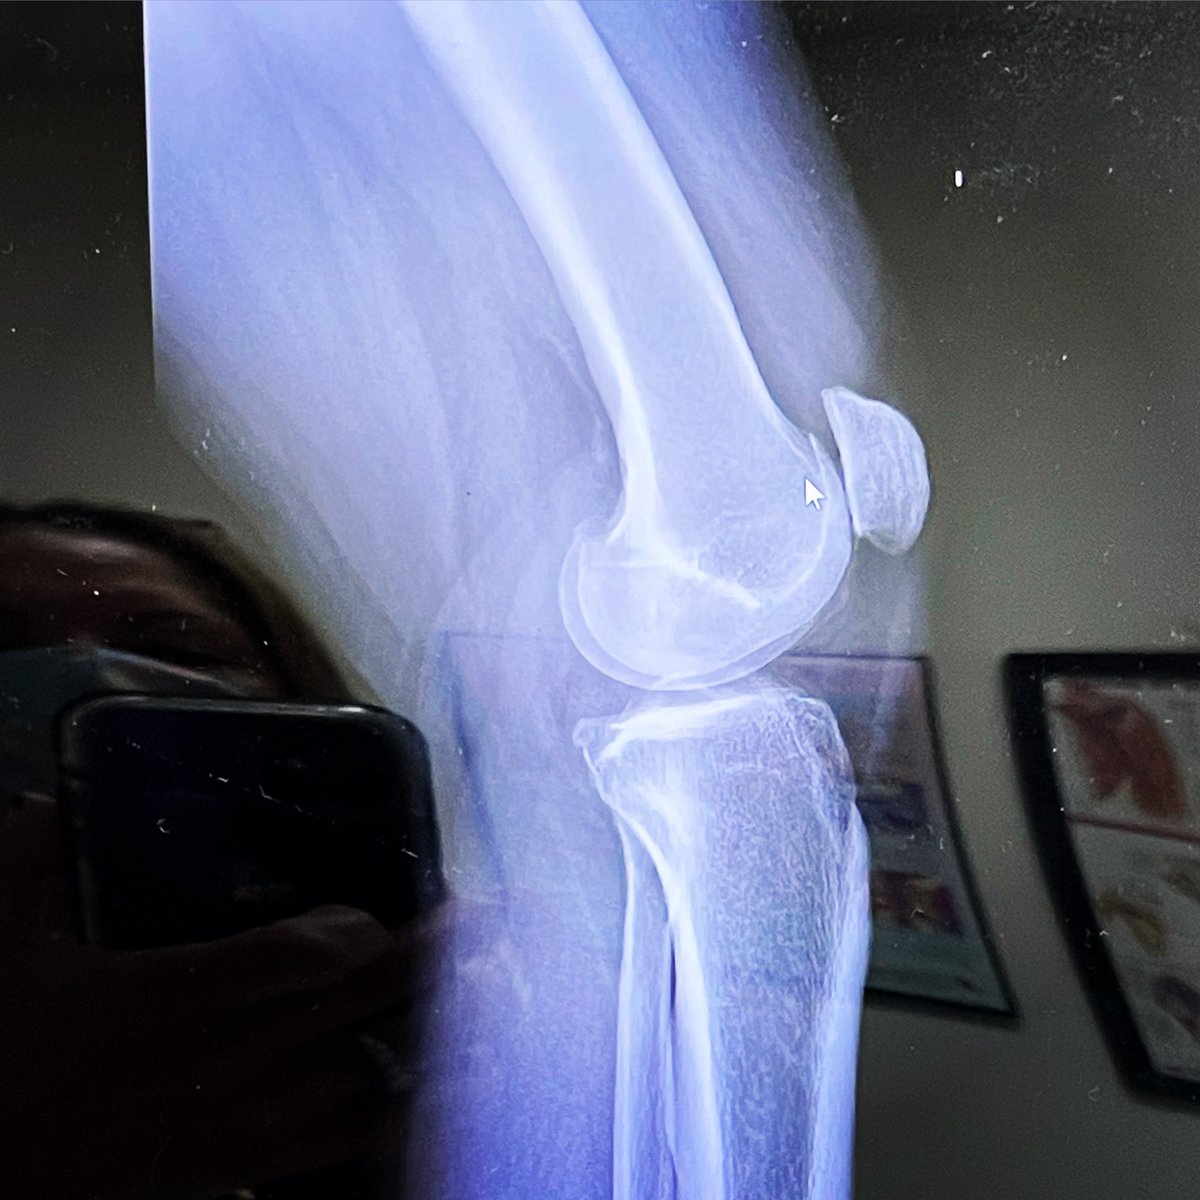

BoneSmart helps joint replacement patients meet the challenges of surgery and recovery Each year we host hundreds of new members and guests looking for information and answers to their questions. Support BoneSmart this Giving Tuesday with a donation. Bonesmart.org